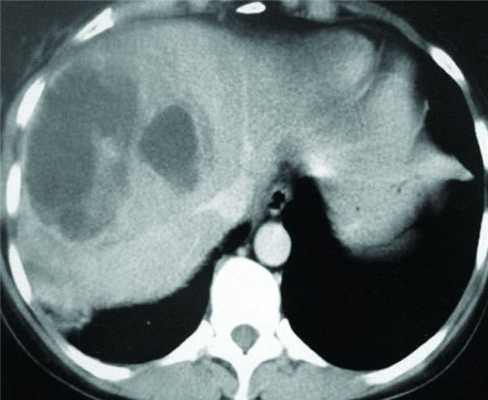

После проведенного антибактериального лечения (амоксициллин 1,5 г в сутки в течение 10 дней без эффекта и цефтриаксон 1 г в сутки в течение недели) наступило незначительное улучшение. Для уточнения диагноза госпитализирован в университетскую клинику ЮУГМУ 18.03.16, где диагностирована нагноившаяся киста левой доли печени. Пациента перевели в ЧОКБ 23.03 и на следующий день выполнили МСКТ органов брюшной полости с контрастным усилением, при которой обнаружены полости в паренхиме печени с нечеткими контурами сливного характера, расположенные в III, IV, VII, VIII сегментах печени, общим размером 100×85×95 мм» (см. рисунок). Мультиспиральная компьютерная томограмма от 24.03.16.

25.03 выполнено пункционное дренирование абсцесса печени под ультразвуковым контролем двумя дренажами с промывной системой. При этом одномоментно эвакуировано 90 мл густого гноя. Послеоперационное течение без осложнений. При контроле (ультрасонография 28.03 и МСКТ 06.04) отмечено спадение стенок гнойной полости. При микроскопическом исследовании пунктата в препарате найдено большое количество лейкоцитов, внутриклеточных бактерий, цисты лямблий, простейшие не обнаружены. Микробиологическое исследование — роста бактерий нет.